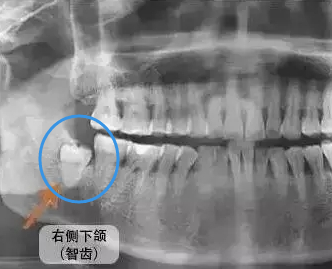

智齒是從(cong) 門牙開始數的第8顆牙齒